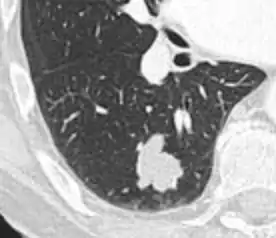

- Margin morphology: a spiculated margin is a risk factor for cancer.[8] Benign causes tend to have a well defined border, whereas lobulated lesions or those with an irregular margin extending into the neighbouring tissue tend to be malignant.[10] In particular, spiculations are highly predictive of malignancy with a positive predictive value up to 90%.[9] Also, a "notch sign", which is an abrupt indentation of the nodule, increases the risk of cancer, but may also be found in granulomatous diseases.[9]

Spiculated lung nodule.[9]